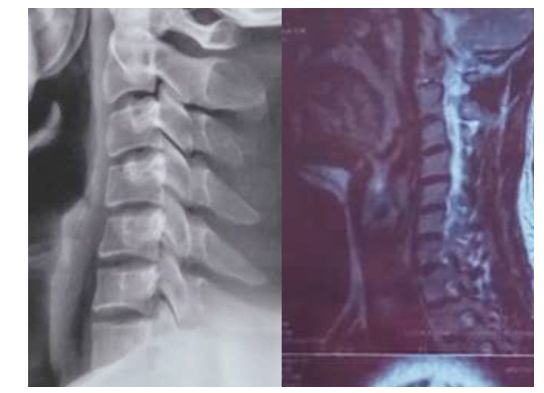

在临床上发现,很多核磁影像与X光影像对比,几乎所有颈椎间盘突出与颈椎变直是同时存在,就不得不考虑颈椎曲度变直与颈椎间盘退化的必要联系。